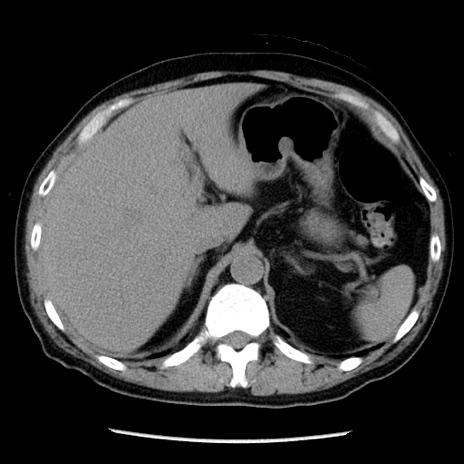

冠状断像

【症例】40歳代男性

【現病歴】2日前から胃痛あり。徐々に周期的な激痛に変化した。本日になっても激痛があるため受診。

【身体所見】意識清明、BT 38-39℃台あり、腹部:膨満、やや硬、右下腹部に圧痛あり。

【データ】WBC 8500、CRP 23.26